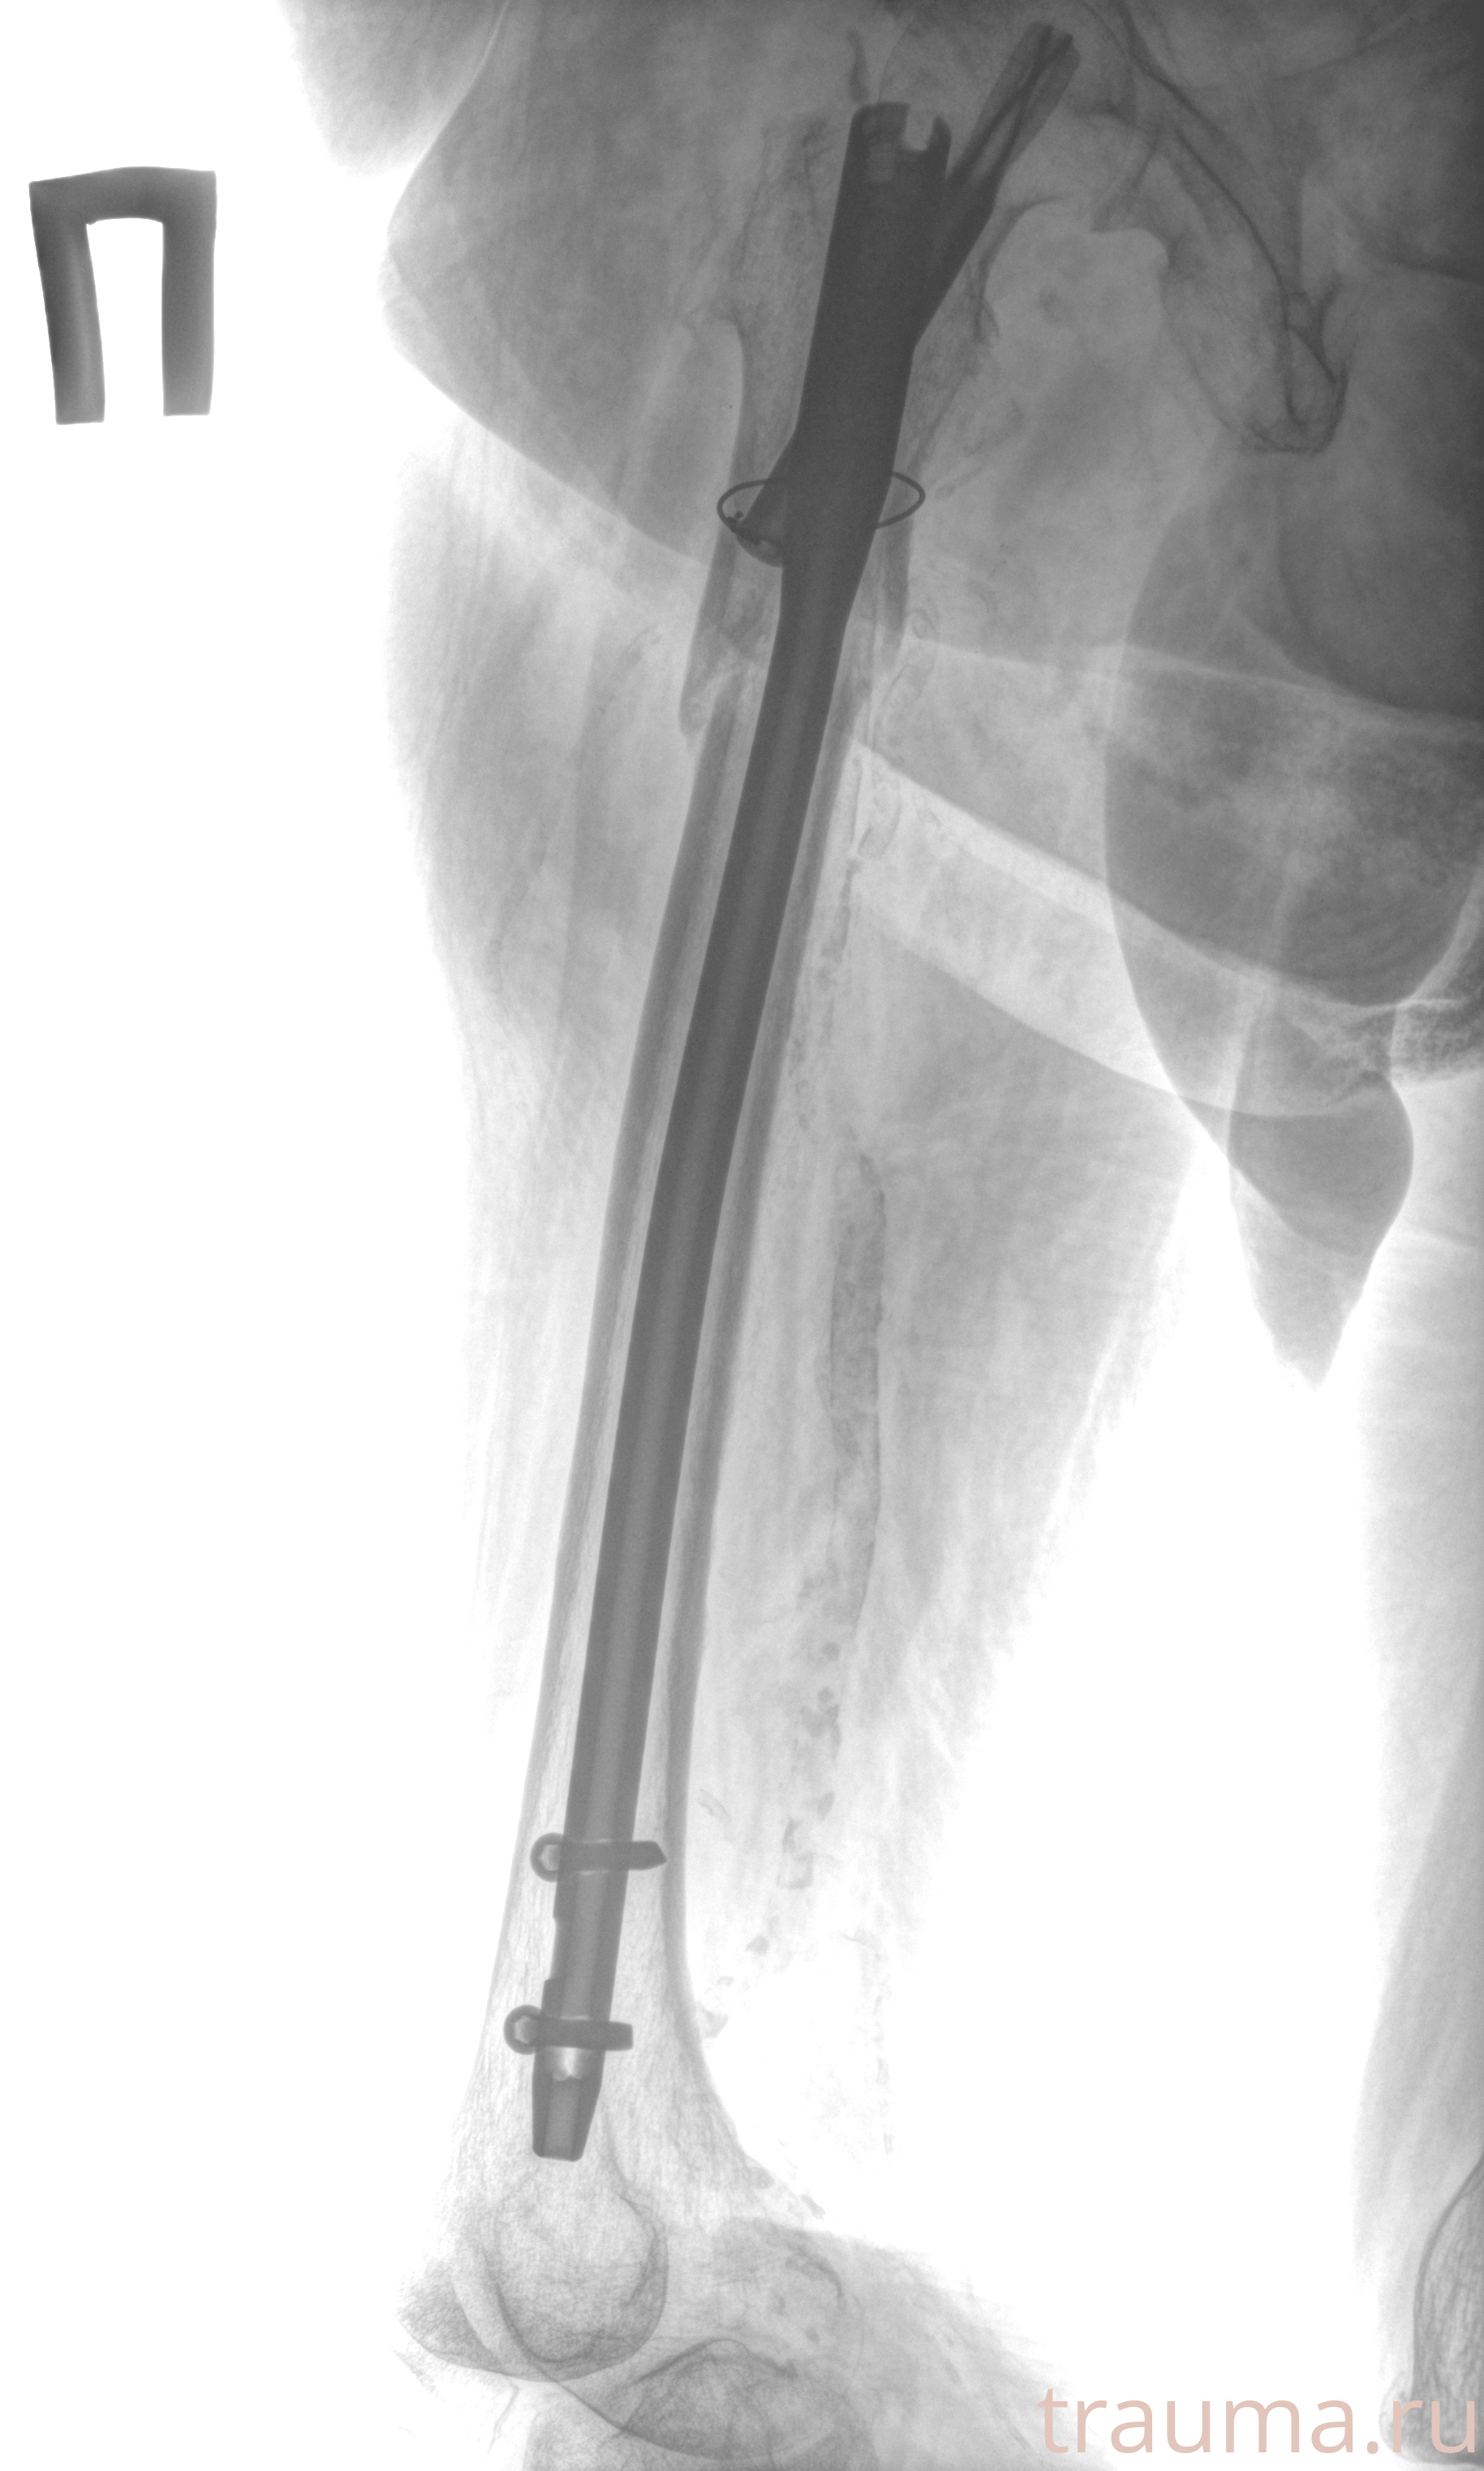

Рентгенограммы